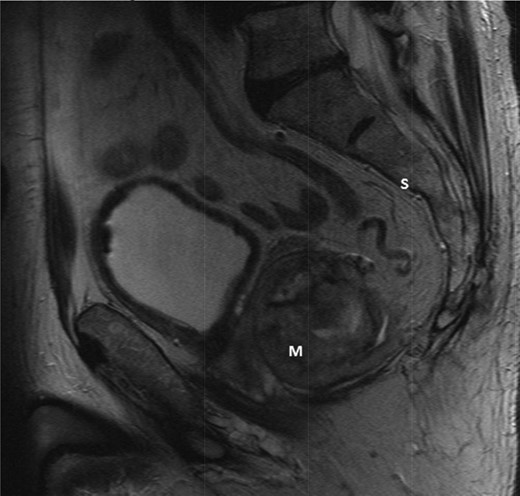

The multidisciplinary team review advised neoadjuvant treatment with imatinib mesylate and further reassessment. Repeat MR pelvis and staging PET CT abdomen, thorax and pelvis were then performed. These showed a large extra-luminal tumour with downsizing in tumour bulk (6 × 5.7 × 5.4 cm) (Figs 3–5) but in close approximation with the right seminal vesicle.

T2-weighted sagittal images after 3 months of imatinib mesylate therapy. The mass has shown a significant reduction in size (Mass = m, Sacrum = s).